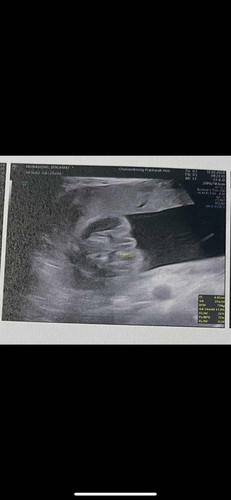

ช่วยดูให้หน่อยค่ะ

แบบนี้ชายหรือหญิงคะ

หญิงค่ะ กลีบชัด